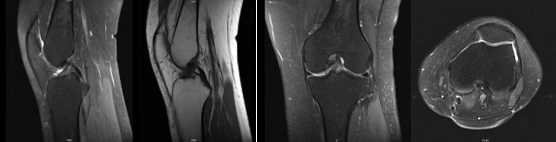

1. 无电离辐射,可以任意方位、多参数成像,提供丰富的诊断信息

(例如膝关节扫描:通过矢状位、冠状位及轴位三种方位,T1WI、T2WI、PD-FSE多种扫描参数提供详细的诊断信息)